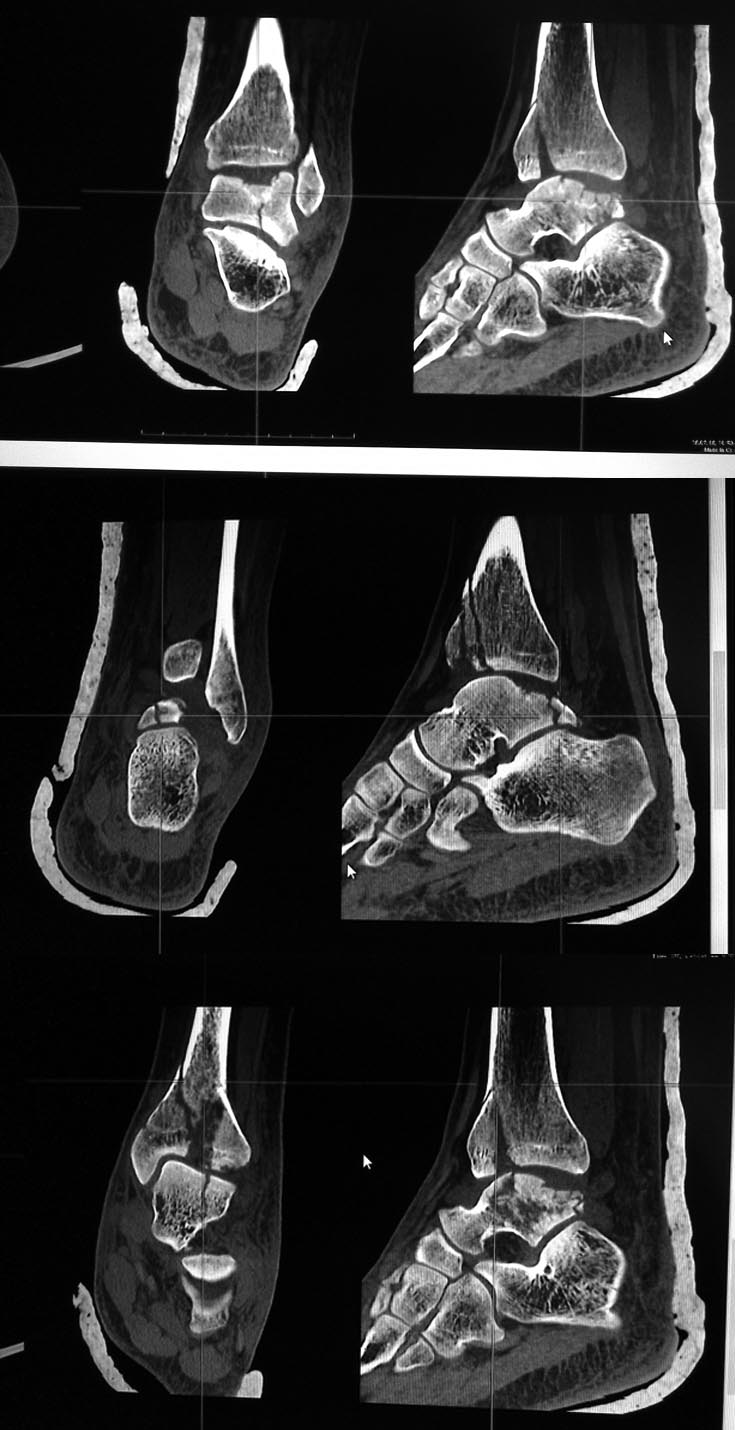

[Ortho] перелом таранной кости и пилона

Глубокоуважаемые коллеги! Помогите определиться с тактикой лечения

перелома таранной кости.

Пациент 29 лет, падение 16.07 с высоты 3 м, травма изолированная,

состояние мягких тканей вполне удовлетворительное для такого

повреждения. Вопрос о возможности оперативного восстановления

оскольчатого импрессионного перелома задних отделов таранной кости.